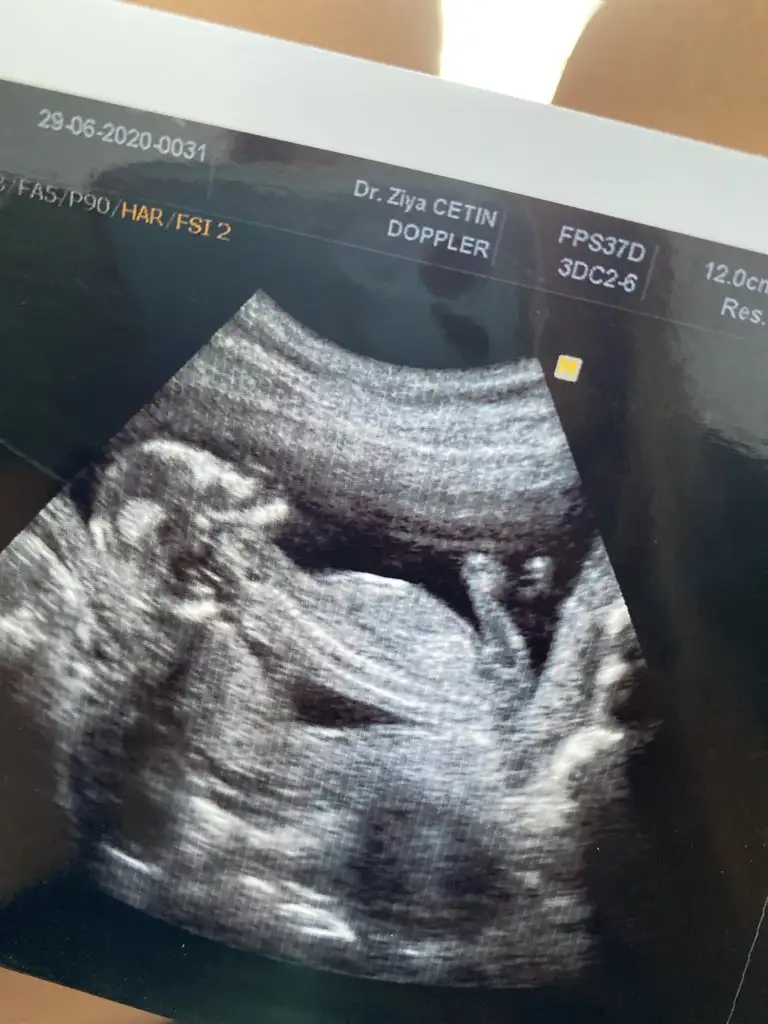

Usgde yazıyor 13+5 digeri yazmıyor 2. Usg de 13 + da nub değil artık organ oluşumu başlıyor ya pipi ya pıtış oluyorSagdaki derken canim yani ilk ustekimi

Net degil nubu sankş kız emin olamıyorum başka usg varmı 11 12 13 haftalarda olurEki Görüntüle 2657612 Eki Görüntüle 2657612

Başka hiç resim yok bu ultrason fotoğrafında 12 haftalıktı. Şimdi 13. Haftadayım ama doktor söylemiyor burda cinsiyetini 20. Haftaya kadar beklememiz lazımNet degil nubu sankş kız emin olamıyorum başka usg varmı 11 12 13 haftalarda olur